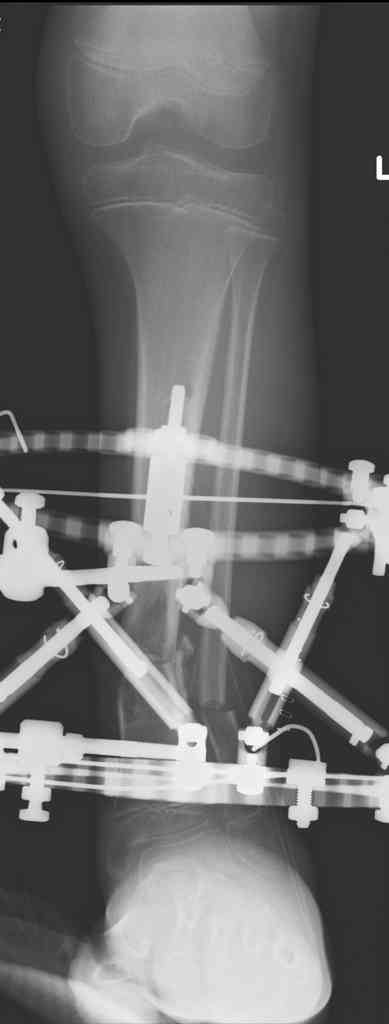

3,4 - через 4 недели наложен спице-стержневой аппарат, произведена остеотомия большеберцовой кости в верхней трети, раны зажили, проводилась дистракция в аппарате.

5, 6 - через 2,5 мес после травмы выполнен закрытый остеосинтез блокируемым штифтом.